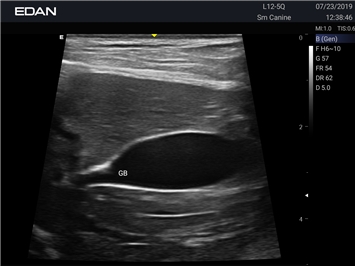

Ветеринарный ультразвук одним нажатием. Система Acclarix AX2 VET разработана с целью обеспечить бескомпромиссную производительность по доступной цене. Наличие уникальных двойных аккумуляторов в легком корпусе массой 4,5 кг из магниевого сплава позволяет системе Acclarix AX2 VET удовлетворять все потребности ветеринарных исследований, сохранив низкую стоимость.

EDAN Acclarix AX2 VET представляет собой специализированную ветеринарную ультразвуковую систему, сочетающую высокую производительность с доступной ценой. Благодаря продуманной конструкции и передовым технологиям, система обеспечивает качественную диагностику животных различных видов.

• Высокое разрешение для детальной диагностики

• Улучшенная визуализация глубоко расположенных органов